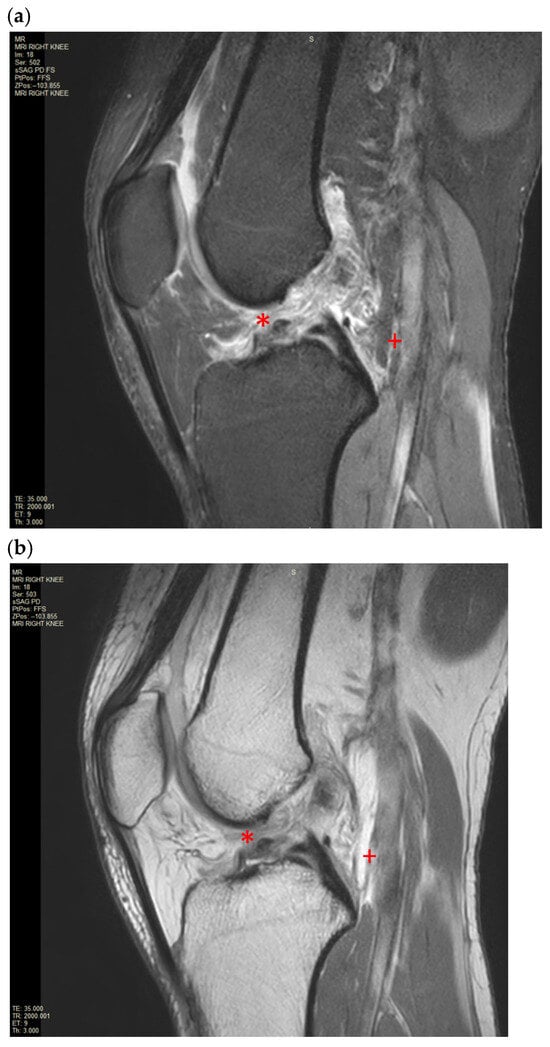

Anterior Cruciate Ligament Rupture with Concurrent Gastrocnemius Tear: A Case Report of a Rare Pattern of Injury

Background, Clinical Significance: Anterior cruciate ligament (ACL) injuries are common, however the occurrence of concurrent gastrocnemius muscle tears is exceptionally rare. Given this, the diagnosis and management of this pattern of injury is poorly characterised, with lack of current clinically relevant classification systems and evidence-based guidelines to guide treatment. Early recognition is essential. with advanced imaging critical to guiding the diagnosis and management of patients with this pattern of injury. Case presentation: A 39 year old man presented with acute right knee swelling, pain and difficulty weightbearing following a sports-related fall. Clinical examination was suspicious for an ACL injury. Magnetic Resonance Imaging (MRI) of the knee demonstrated the disrupted and displaced ACL fibres, with extensive peri-cruciate oedema around the expected position of the ACL. It was associated with partial avulsion of the medial gastrocnemius origin and incomplete avulsion of the lateral gastrocnemius origin. The patient was referred for an urgent orthopaedics review and is currently on trial of conservative management. Conclusions: In this case report and review of the literature, we evaluate the current understanding of the complexities of combined musculoskeletal injuries and limitations of existing classifications in providing accurate diagnosis and management strategies. Given the rarity of this presentation, the case underscores the lack of evidence-based recommendations for early management, particularly in young, active individuals who are at risk of significant long-term functional impact. Full article